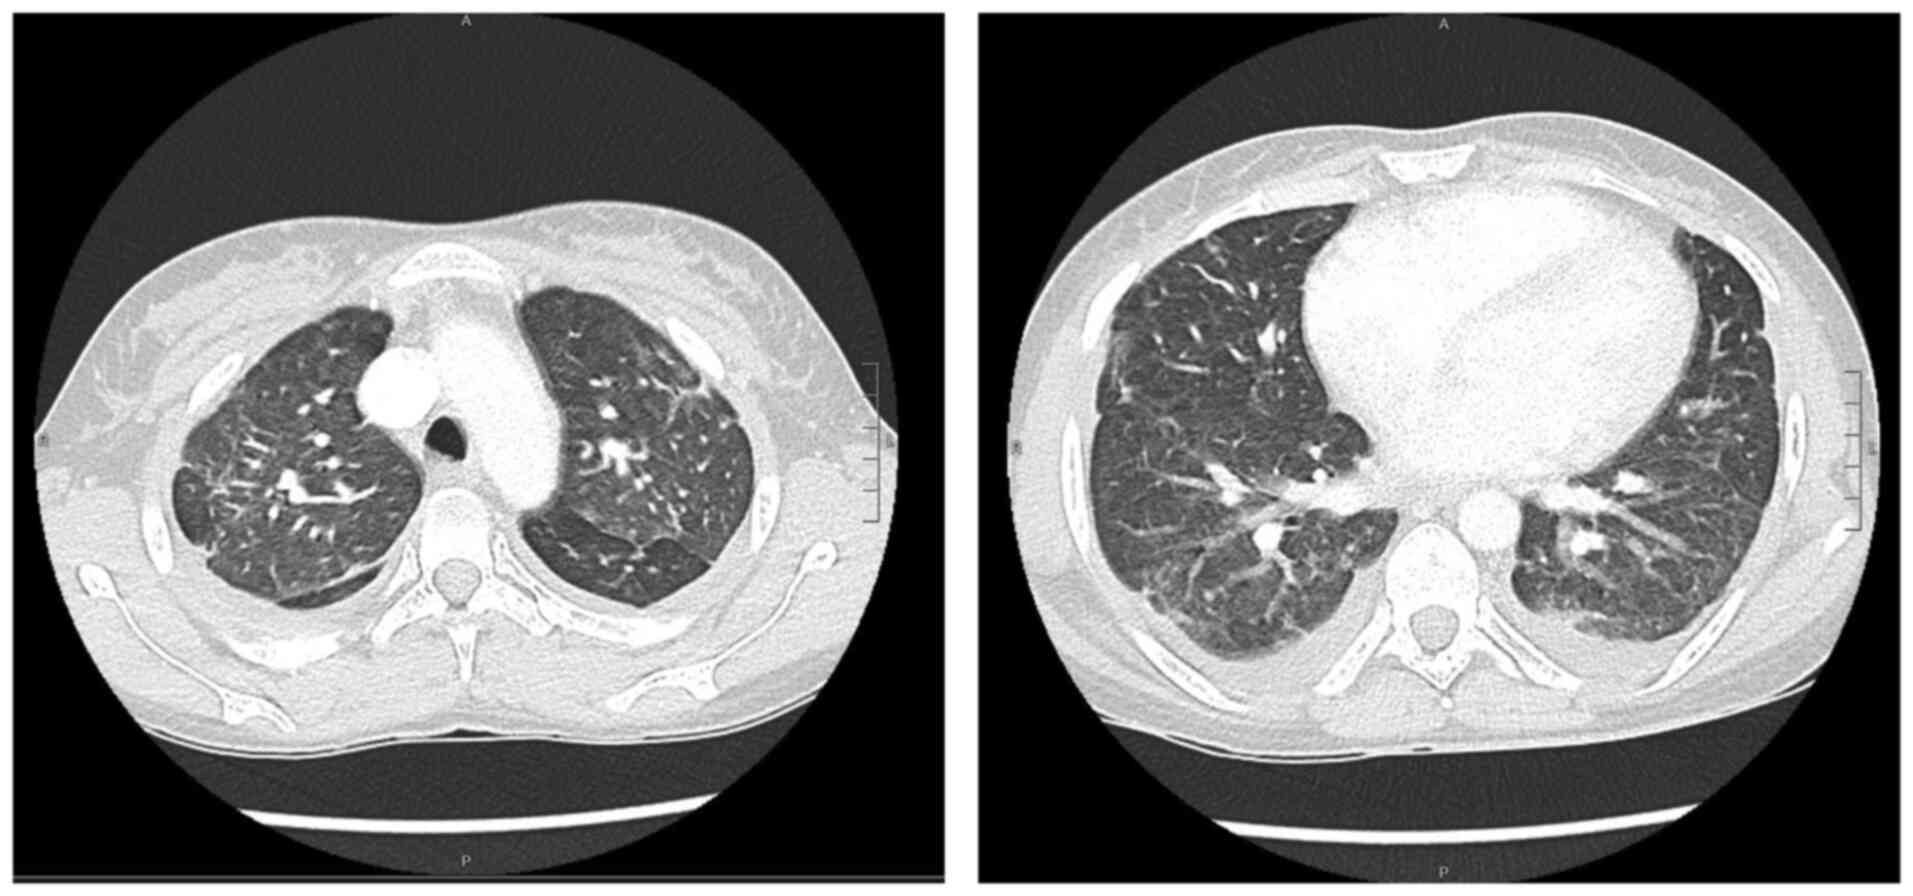

Blood tests revealed mild anaemia with a reduced red blood cell (RBC) count [haemoglobin (Hb), 9.8 g/dl; RBC, 3.34x106/mm3, normal white blood cell count (WBC), increased C-reactive protein (CRP) levels (2.38 mg/dl) along with high erythrocyte sedimentation rate levels (104 mm/h), increased total bilirubin levels (2.85 mg/dl), aspartate aminotransferase at 83 U/l and alanine aminotransferase at 56 U/l. Creatinine levels and liver function marker (coagulation and albumin) levels were normal (creatinine level, 0.56 mg/dl; international normalized ratio, 0.98; and albumin, 3.8 g/dl). Hepatitis B virus (HBV) and hepatitis C virus (HBC) along with human immunodeficiency virus (HIV) tests were negative. A chest X-ray revealed right medio-basal lung consolidation with a perivascular interstitial thickening (Fig. 1). Thorax computed tomography (CT) scan images (acquired before and after contrast administration, using a SOMATOM® Definition Flash scanner; Xenetix, 350 mg/ml; Siemens AG) revealed bilateral ground glass opacities with interlobular septal thickening, lower lobes consolidations and bilateral pleural effusion (Fig. 2), whereas an abdomen CT scan revealed homogeneous hepatomegaly, and a 3 cm densely calcified spleen (Fig. 3).

Figure 1

Chest X-ray showing interstitial involvement along with right basal consolidation.